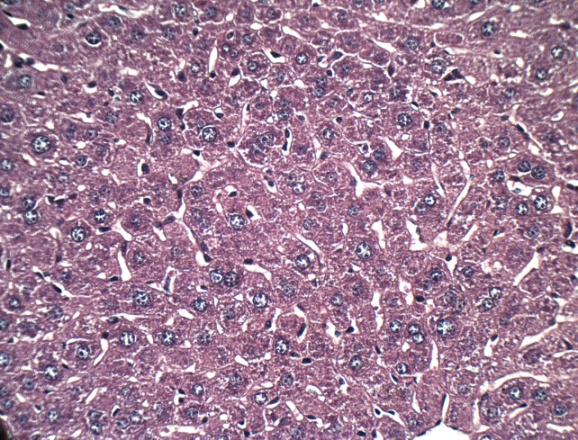

Histopathology

Histological profile of the normal control group revealed normal histology of liver with central vein, hepatocytes and portal triads. MTX induced group revealed marked degree of centrilobular necrosis along with polymorphonuclear cells infiltration, severe vacuolations in the hepatocytes and sinusoidal congestion. Pre-treatment with LIV-52 reduced MTX induced microscopic changs and showed marked beneficial effects in the liver architecture. Ambrex treatment at the low dose showed moderate degree of necrosis, mild degree of vacuolations in the hepatocytes with minimal sinusoidal congestion. Ambrex administration at high dose revealed regeneration of hepatocytes to normal architecture, absence of sinusoidal congestion and vacuolations in the hepatocytes. On the basis of the above observation, it is concluded that pre-treatment with Ambrex at high dose (500 mg/kg b. wt. p. o) have hepatoprotective activity against MTX induced hepatotoxicity (fig. 4).

A B

C D

E

Fig. 4: Representative photograph showing the effect of Ambrex on MTX induced mice liver-H & E stain X400 magnification. (A) Normal control, (B) Positive control (C) MTX+LIV 52, (D) MTX+Ambrex (250 mg/kg b. wt., p. o.) and (E) MTX+Ambrex (500 mg/kg b. wt., p. o.) treated group